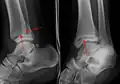

AP manual stress view showing a deltoid ligament tear

A specialized AP stress view of the ankle is performed when there is concern for an unstable ankle injury. There are two types of stress views: gravity and mechanical.[10] In the gravity stress view, the patient lies in the lateral decubitus position with the ankle dangling over the edge of the table to mimic the mechanical stress view.